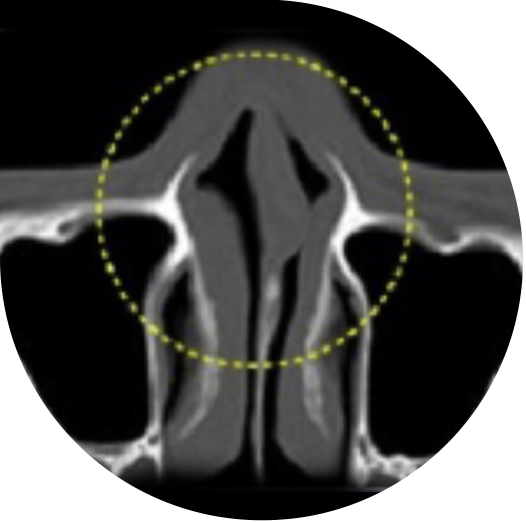

鼻中隔湾曲症

鼻中隔とは、鼻の中央に垂直に軸を成し、鼻の穴を分ける壁のことをいいます。

この鼻中隔が曲がったり、ねじれたりしている状態を鼻中隔湾曲症といいます。

鼻中隔が曲がった状態によって鼻中隔湾曲症C型とS型に分類することもあり、鼻づまり、鼻炎、

蓄膿症などの機能的な障害を引き起こします。

鼻中隔湾曲症の

手術ノウハウ

鼻中隔が曲がった状態に応じて、曲がった部分の鼻中隔軟骨を除去し、

残った鼻中隔軟骨を利用して鼻先の形や高さを正しく矯正します。

手術前 曲がった鼻中隔

手術後 まっすぐに矯正された鼻中隔